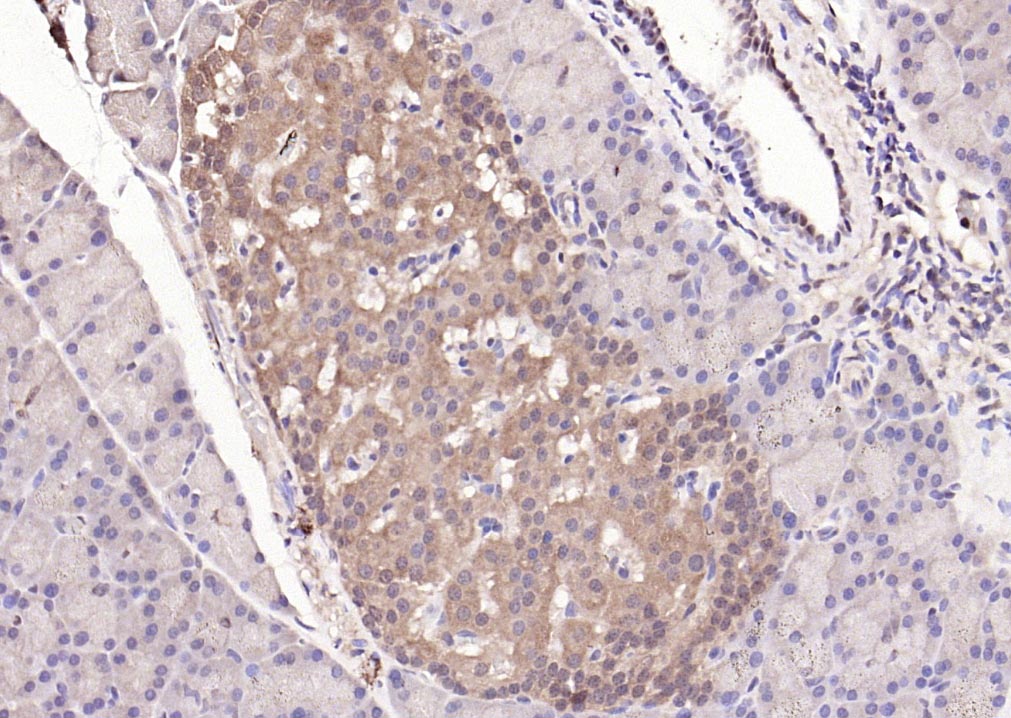

| IHC-P | Human, Mouse, Rat | Cow | 1:200-2000 |